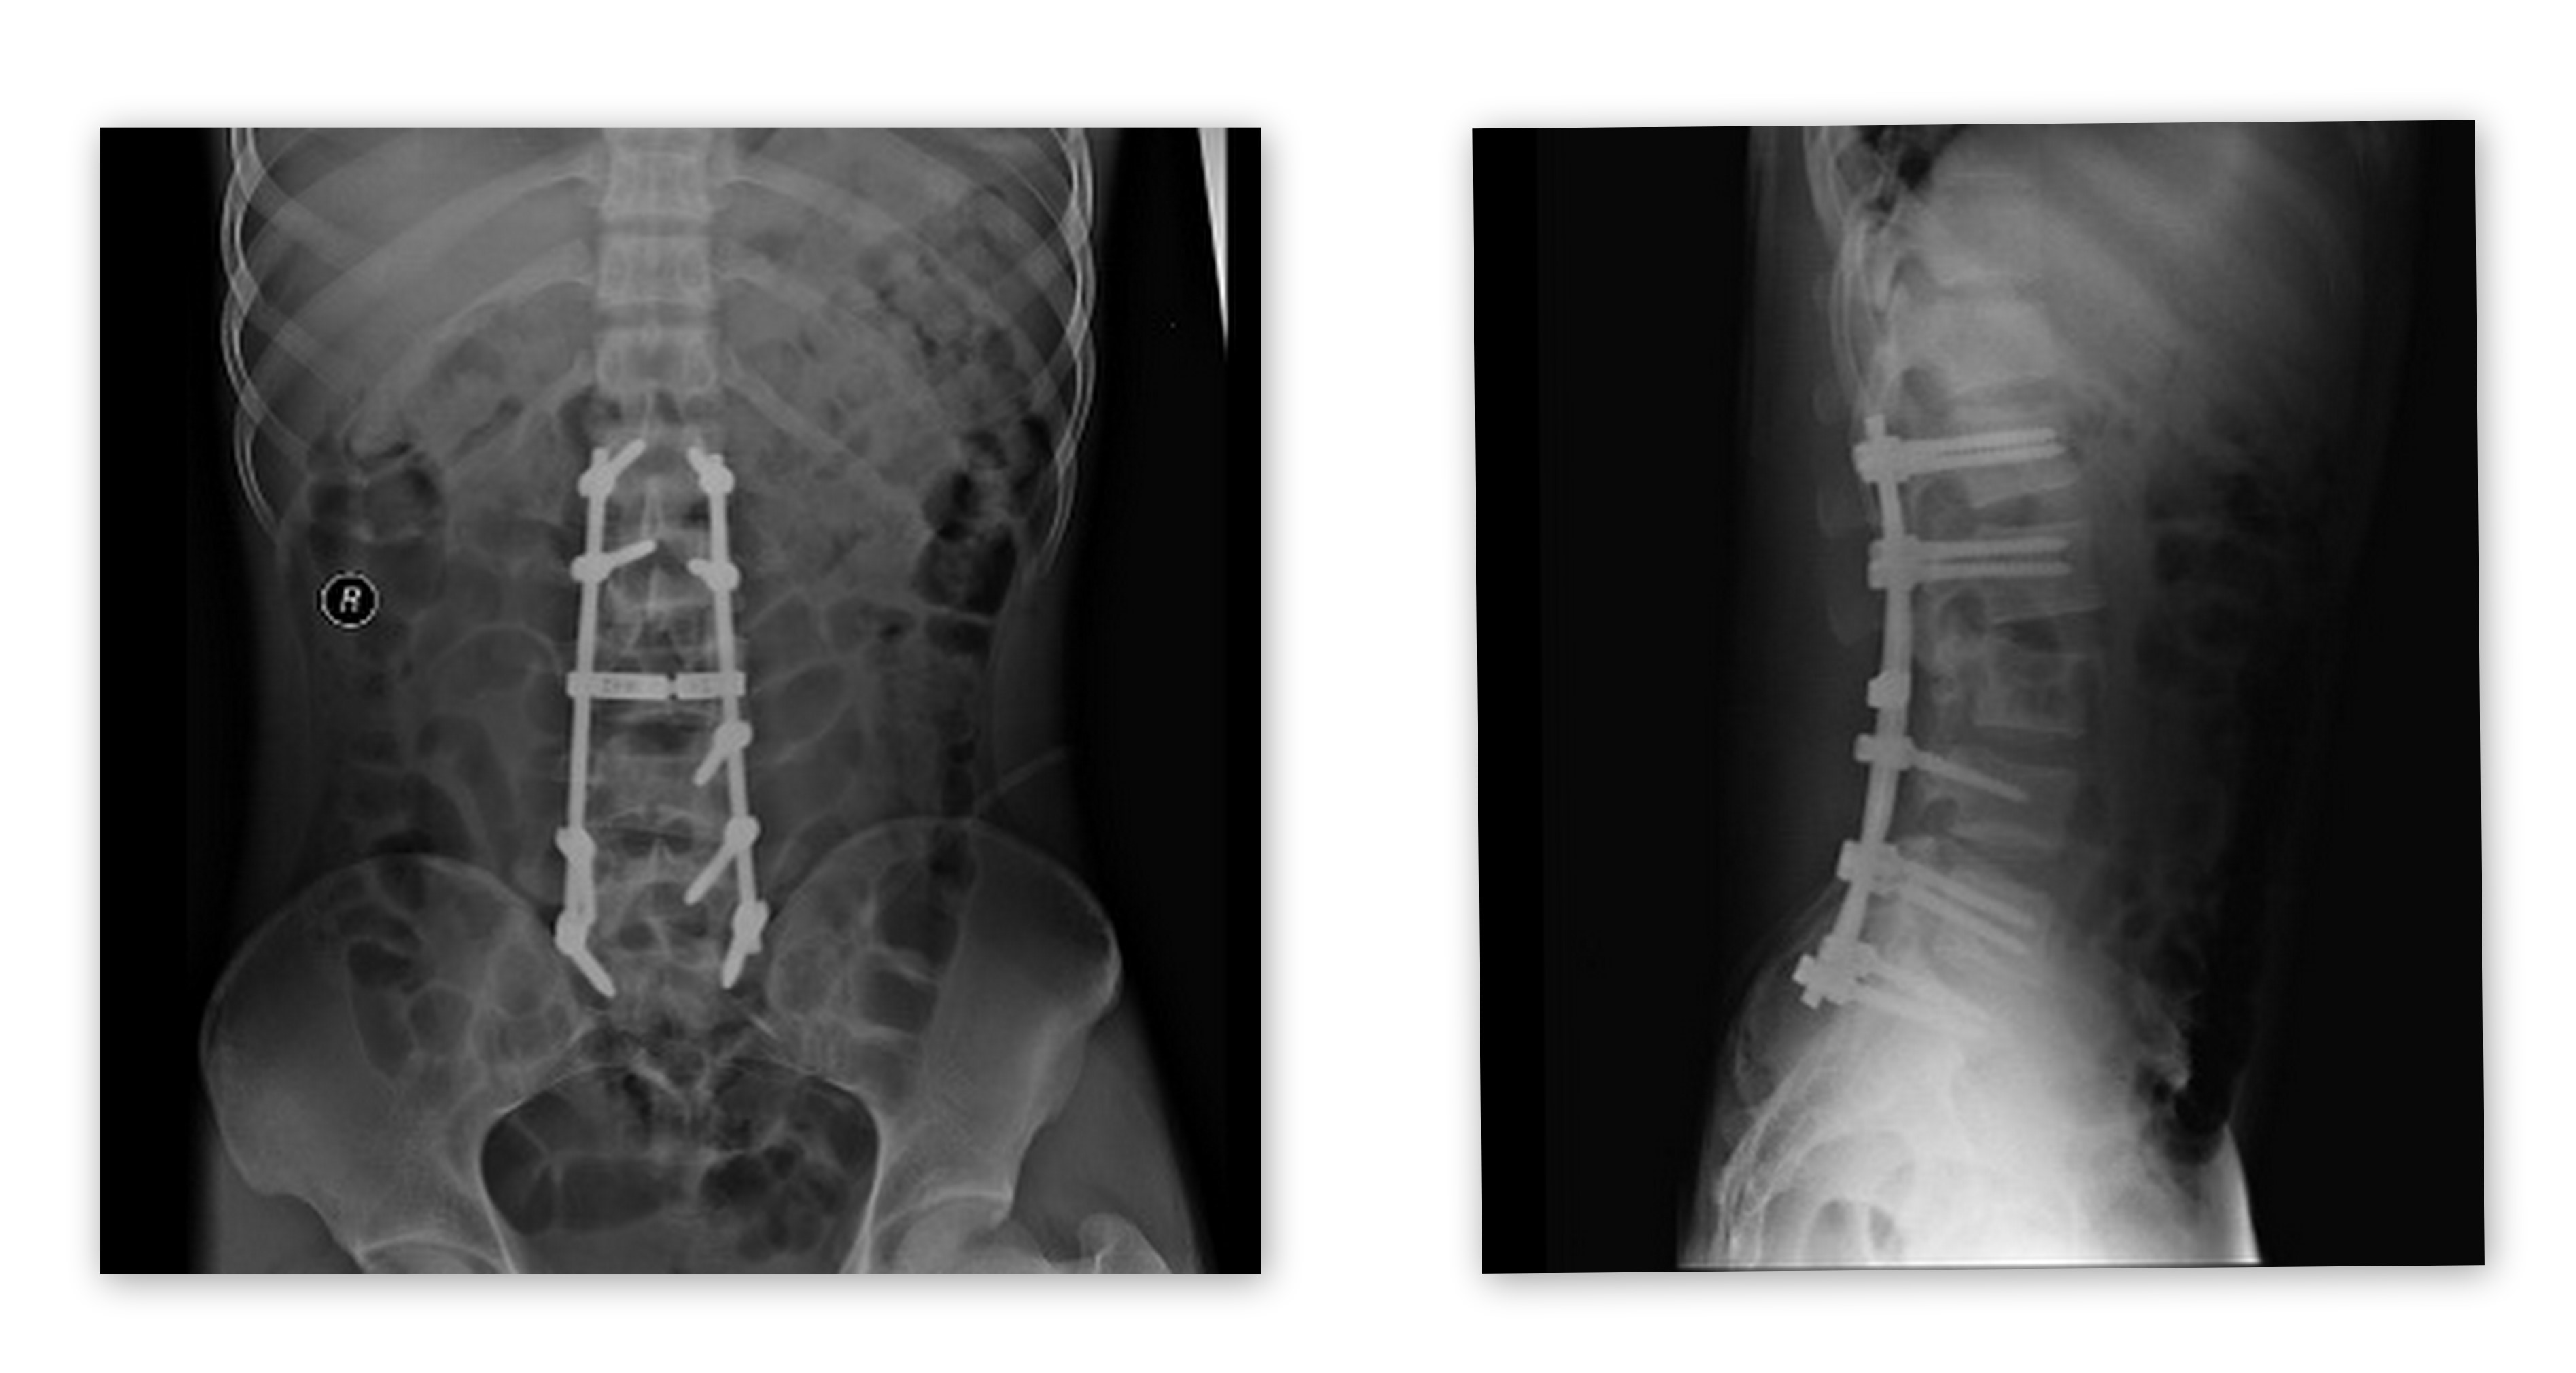

复位术后X光片

术后X线片复查显示,患者腰椎冠状位及矢状位的平衡恢复良好,腰椎骨折解剖复位。椎弓根钉置钉位置准确稳定。术后患者神经功能恢复很快,左小腿肌力2级右小腿3级,并恢复了自主排尿排便功能。(宣传中心 匡远深)